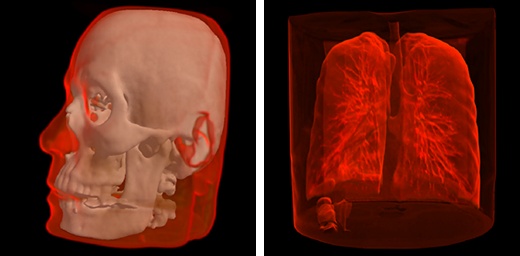

Combined surface and volume visualization mode.

Segmented Data Visualization¶

User can select ROI (Region of Interest) during segmented data visualization.

Special automatic segmentation methods are implemented for the lungs data and skull tissues separation from brain.